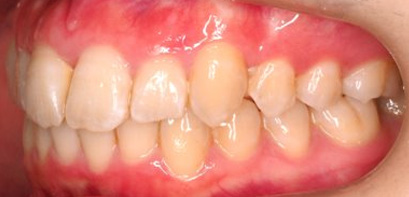

乱ぐい歯、でこぼこがとても酷い状態になります。歯が前後的に重なってしまっている、八重歯になっているなどがこのジャンルに入ります。

顎の大きさと歯の大きさのギャップが大きく、時には歯を抜かないと矯正治療ができない場合もあります。当院では治療期間が長くなるが抜かない治療方針など、一つの治療プランだけでなく、さまざまな可能性の治療方針を説明させて頂くよう心掛けております。こういった考え方はインフォームド・チョイスと言われ近年大切にされている考え方と言われております。

治療前

治療終了前